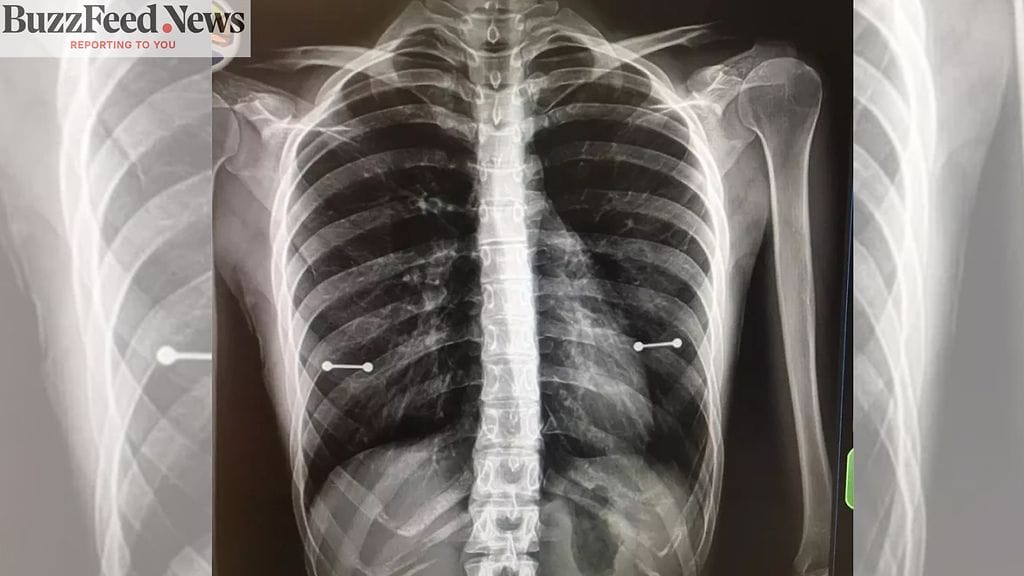

Allenilla on kuitenkin harvinainen tila, joka vaikuttaa hänen selkärankaansa. Rutiinitarkastuksessa Allenista otettiin röntgenkuva.

Röntgenkuva narautti lävistetyn

Kun lääkäri esitteli röntgenkuvaa, Allen äiteineen havaitsi kaksi lävistyskorua kuvassa nännien kohdalla.